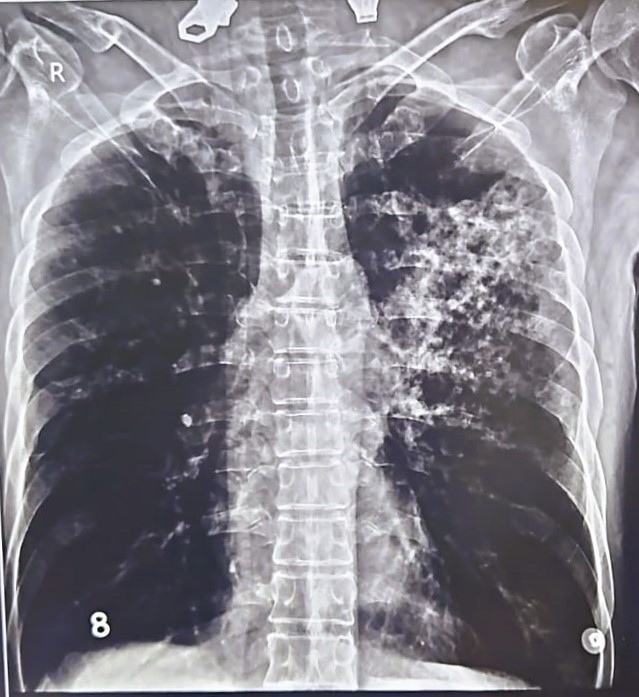

| 205 | IGGMC, Nagpur, Nagpur | P2 | 29-4267 | MOHAMMAD HANIF SUREYYA | Consent taken on Paper | 55 Yrs. |

Provisional Diag : PTB?

Final Diag : PNAEMOTHORAX /CLINICALLY DIAGNOSED PTB |

TB Case (Confirmed) | LEFT SIDED PNAEMOTHORAX | Abnormality visible on x-ray |

View |

|||